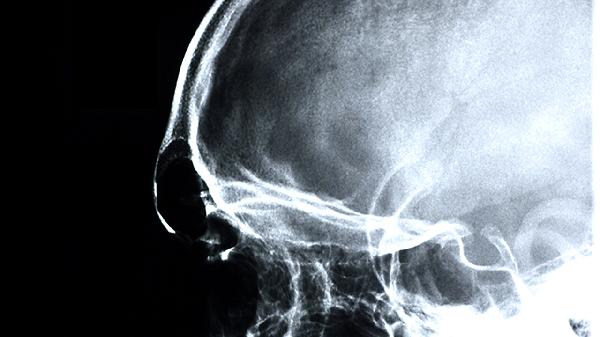

脑供血不足的症状主要有头晕、头痛、视物模糊、肢体麻木、短暂性意识丧失等,可以遵医嘱使用阿司匹林肠溶片、尼莫地平片、盐酸氟桂利嗪胶囊、银杏叶提取物片、血塞通片等药物。脑供血不足可能与动脉粥样硬化、颈椎病、高血压等因素有关,建议及时就医明确病因。